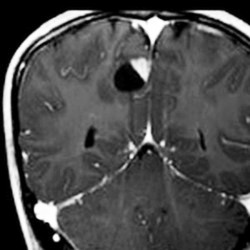

大脳皮質の毛様細胞性星細胞腫

小児期の右大脳頭頂葉にできた毛様細胞性星細胞腫です。小脳と同様に大脳にも壁在結節を作ってのう胞性増大する毛様細胞性星細胞腫というのはよくみかけます。てんかん(けいれん)発作で発症するものが多いです。腫瘍を摘出すると症候性てんかんが止まることが期待できます。治療方法は手術摘出です。腫瘍のある場所が深部で摘出術が神経脱落症状を招くと考えられる場合には,経過観察して,増大するようならガドリニウム増強される腫瘍実質部分にだけ,定位放射線治療することもあります。